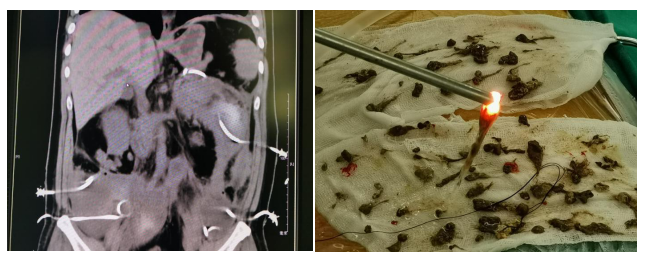

(左)广泛的腹膜后坏死合并感染 (右)肾镜清除出来的坏死组织

该研究建立的胰腺周围坏死组织清创方法对于坏死性胰腺炎合并感染的治疗具有重要意义。该方法丰富了坏死性胰腺炎的治疗手段,证实了阶梯递增治疗方法的有效性,为广泛腹膜后坏死感染这个临床难题提供了宝贵的治疗经验。与国际同类研究相比,该研究纳入病例复杂程度很高(复杂清创比例占54.9%),而死亡率很低(死亡率仅为6.1%)。领导这项研究的董家鸿院士表示:“本研究建立的系列新技术符合精准外科理念,安全、微创、高效,值得广泛推广,造福更多重症胰腺炎患者。”